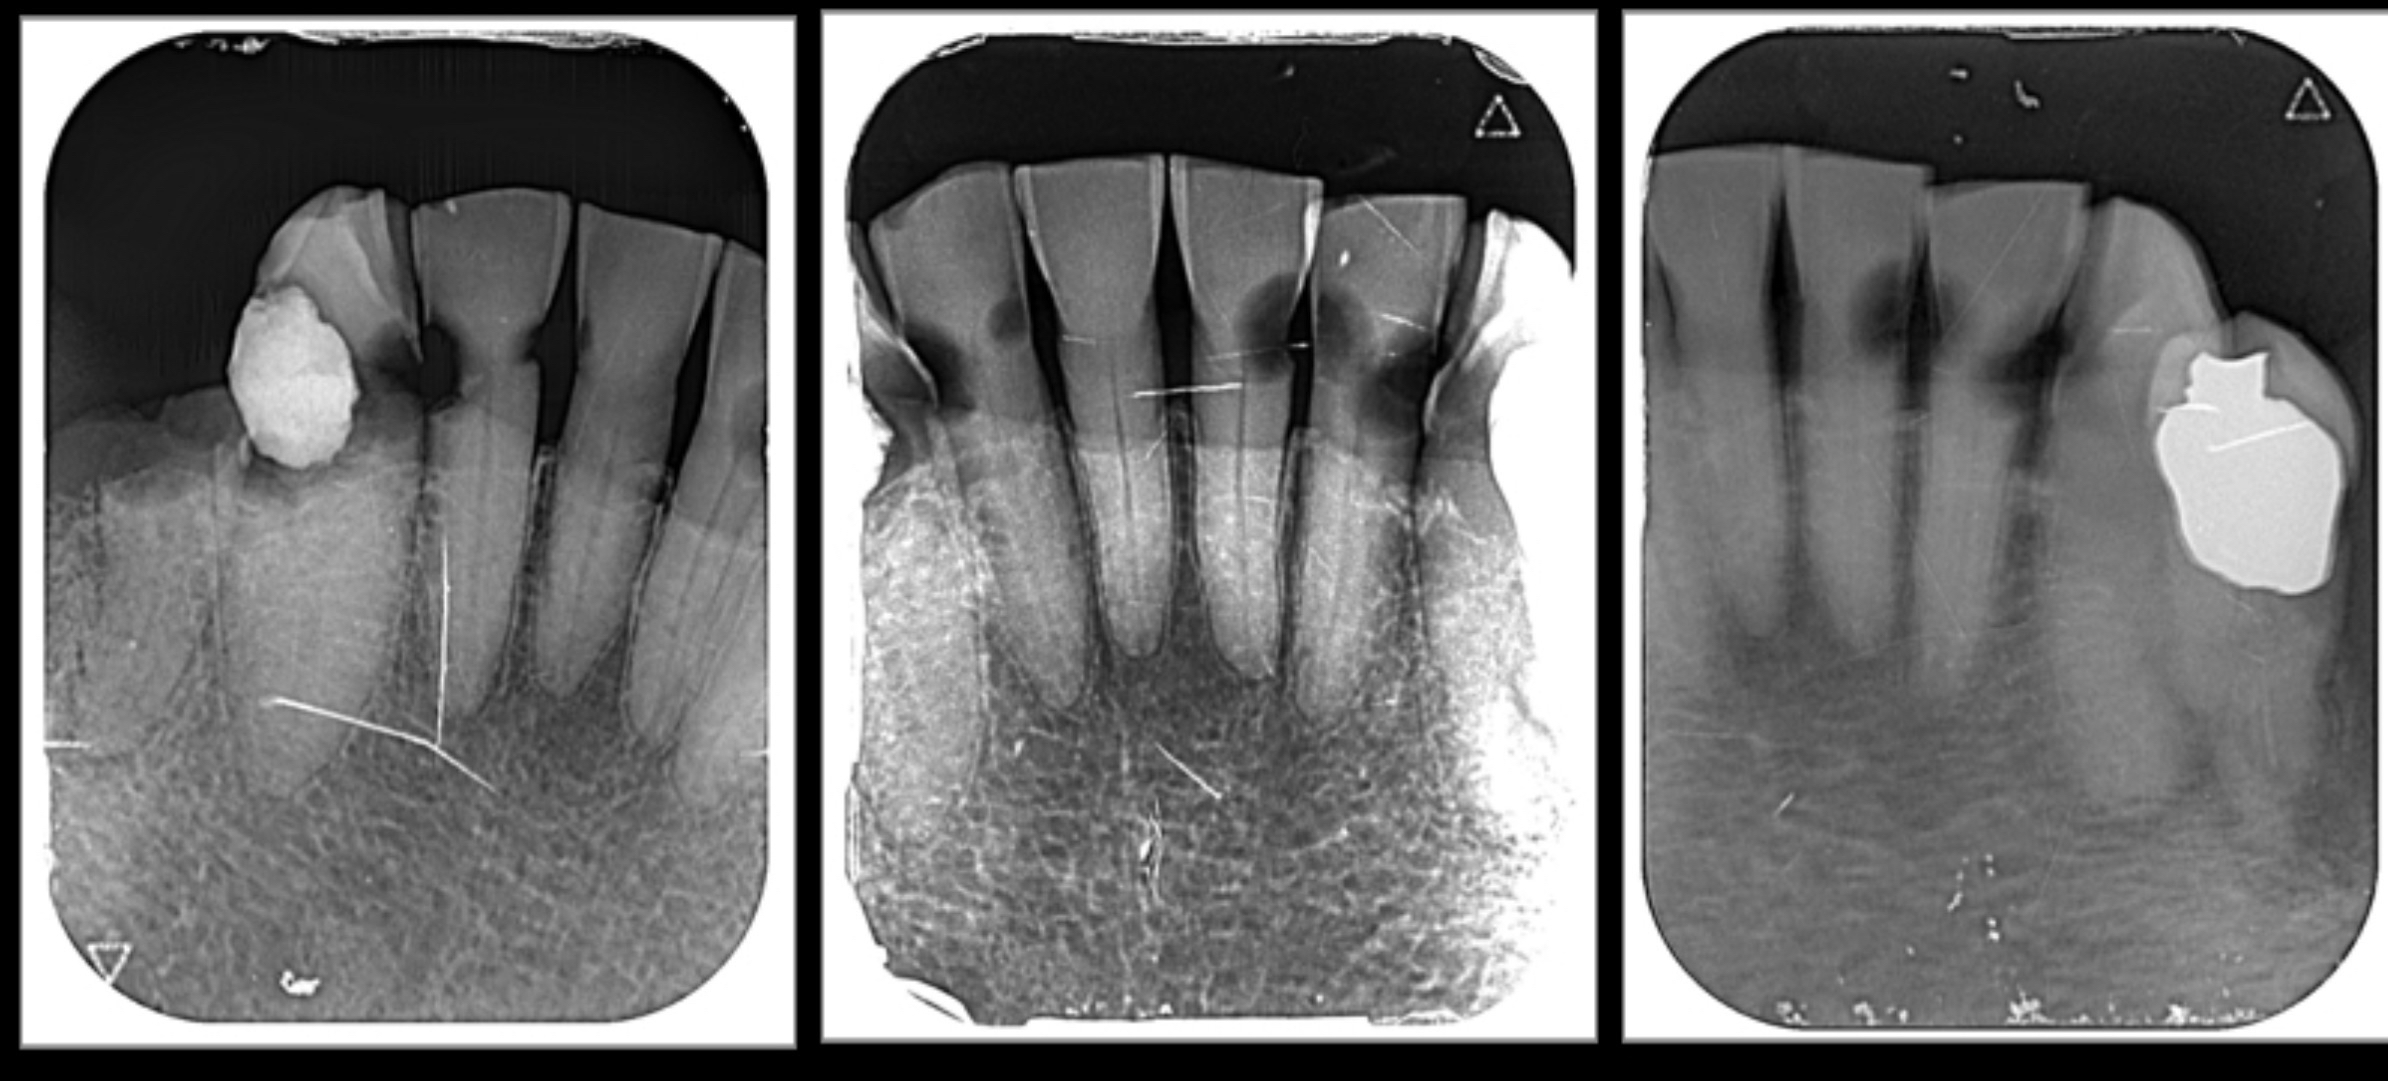

※フロスをしない大人